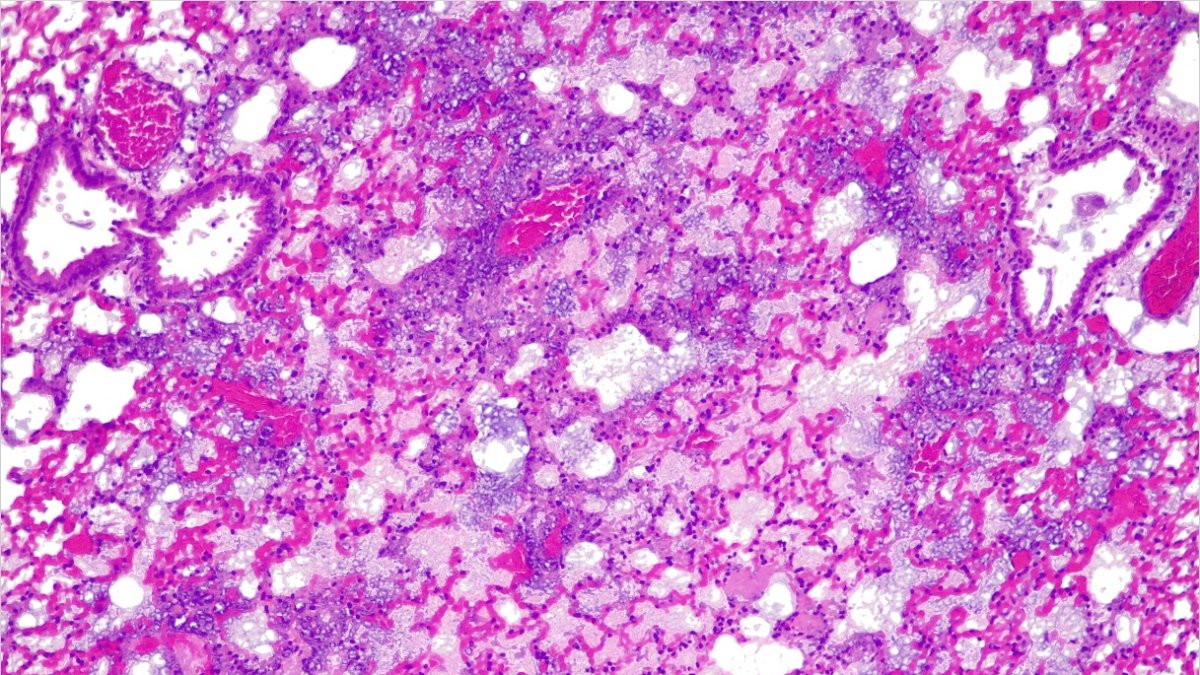

Pulmones de ratón sin píldora activa.